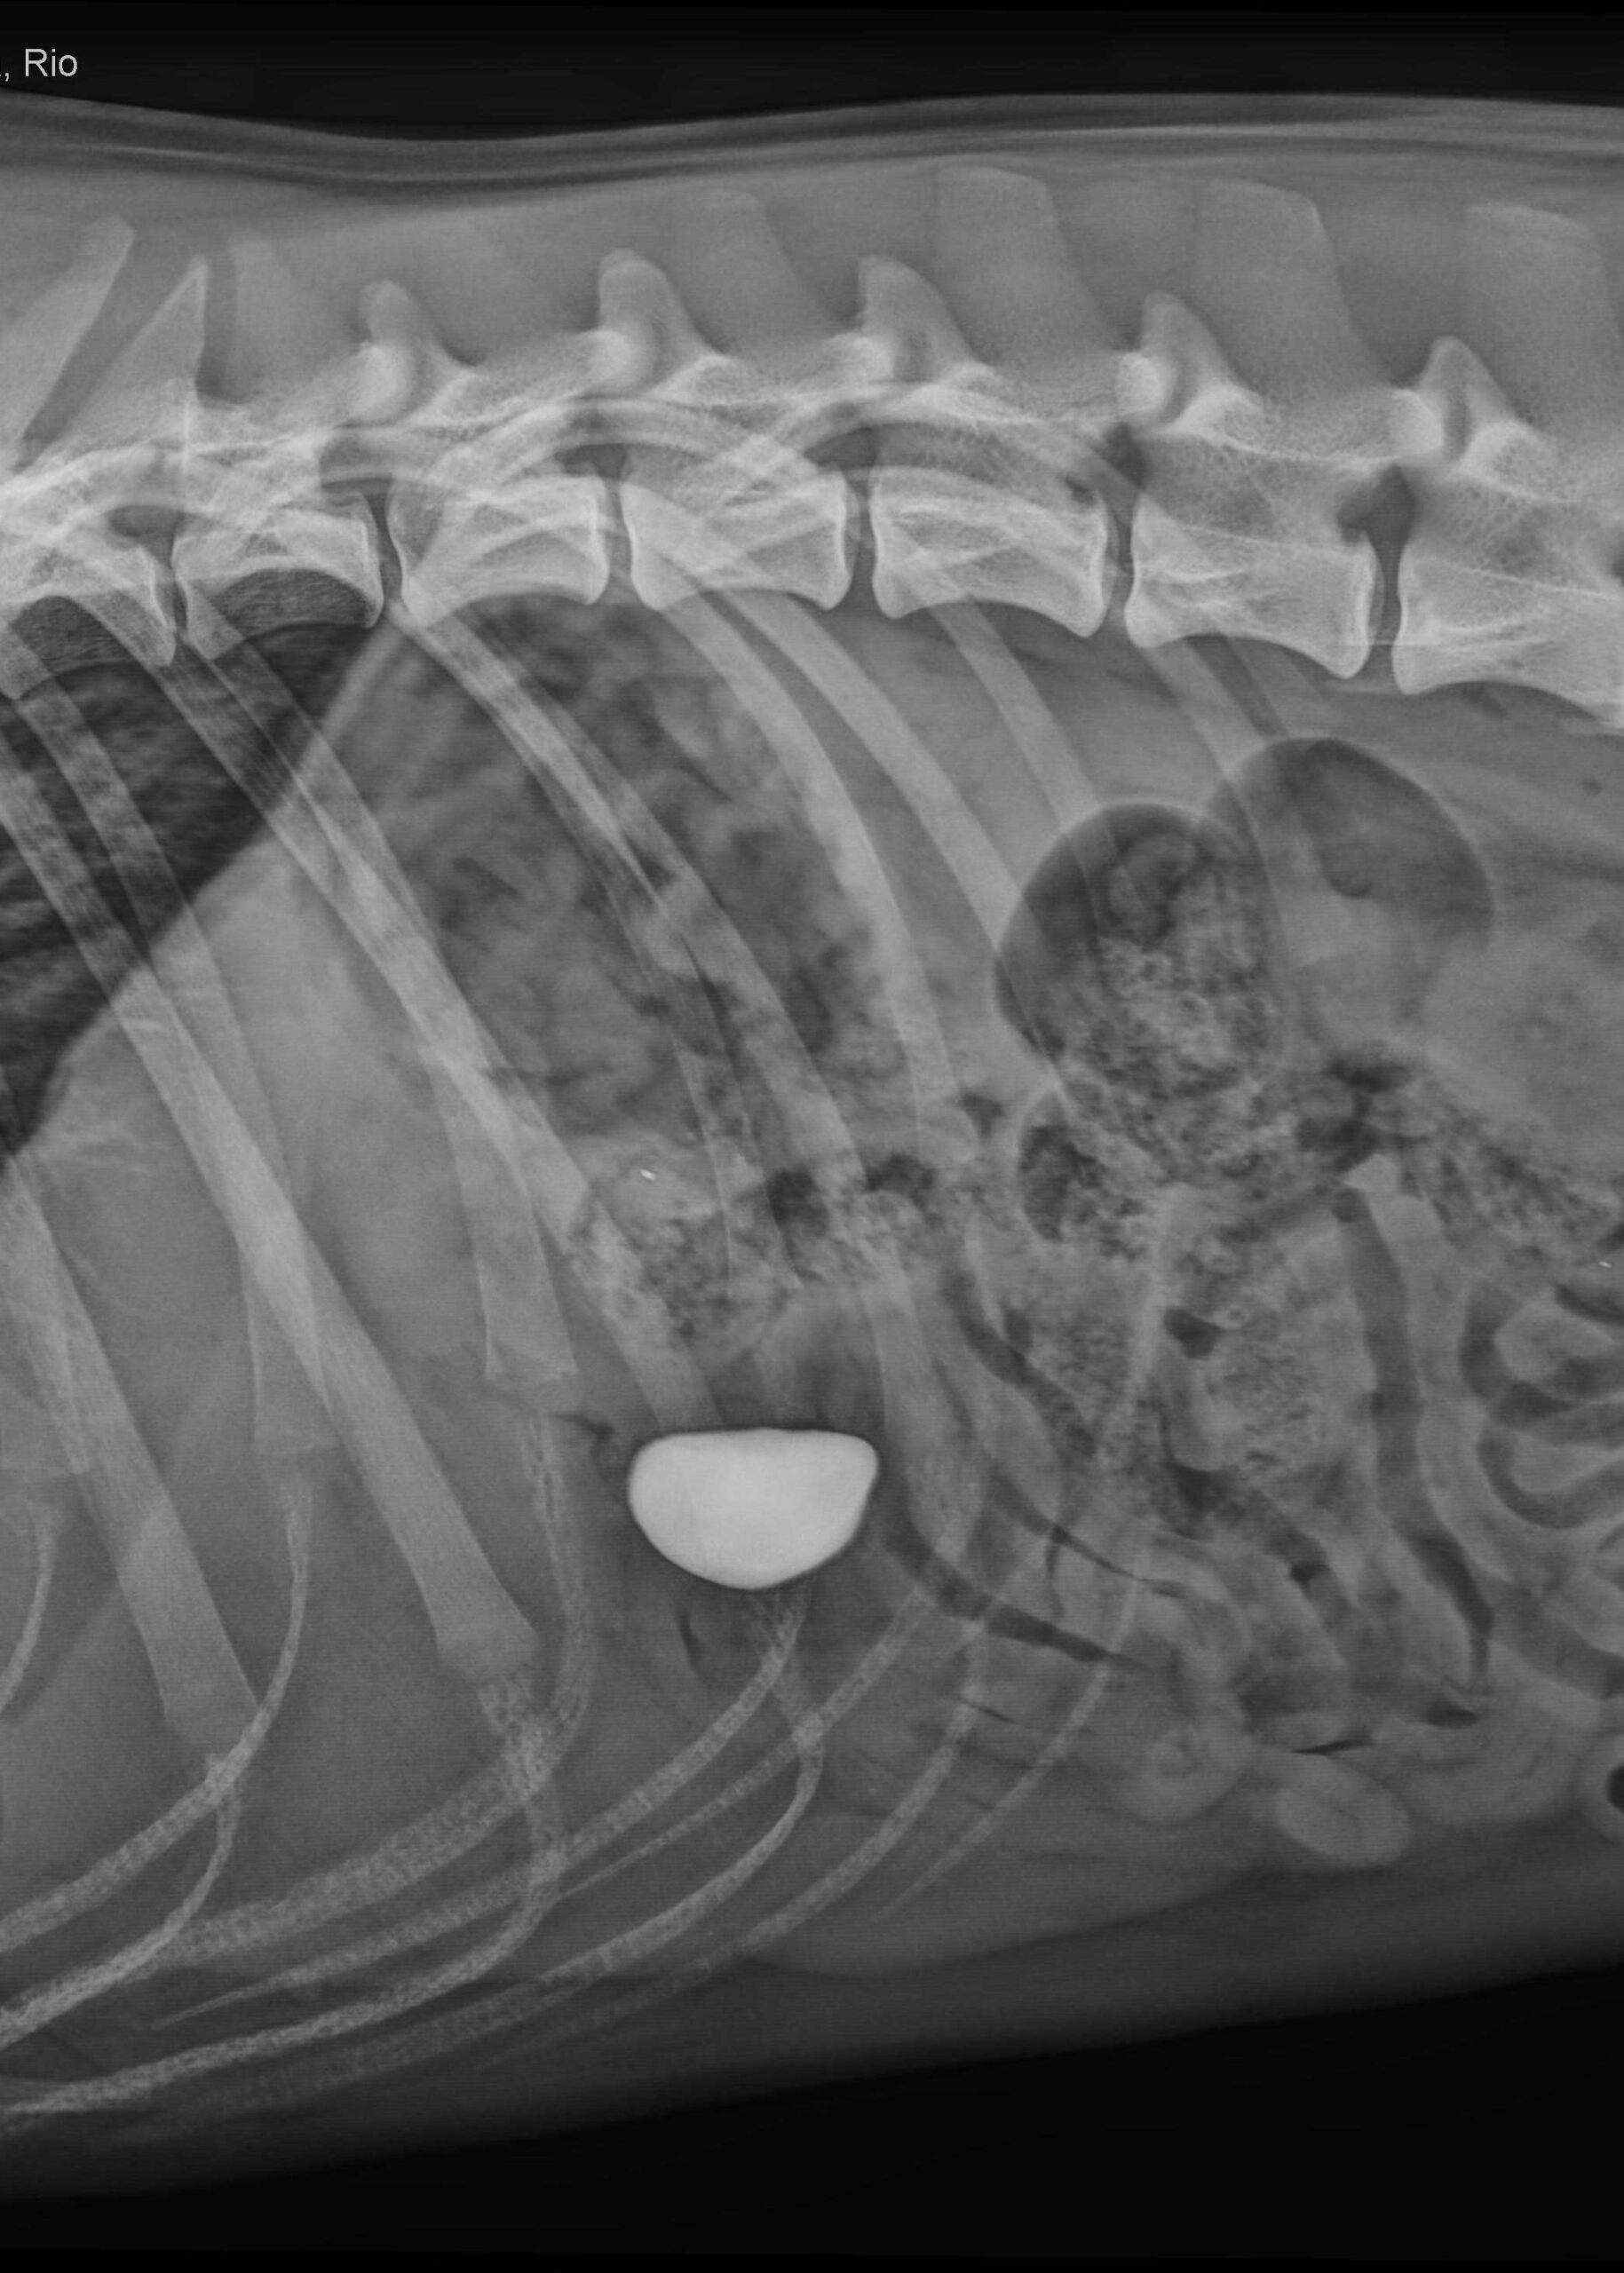

„Der Hund war gestresst und schwer zu untersuchen, aufgrund des stark angespannten Bauches war das Abtasten kaum möglich. Rio hatte eine leicht erhöhte Temperatur, ansonsten war er klinisch unauffällig. Umso wichtiger war die bildgebende Diagnostik. Das Röntgenbild zeigte eine deutlich röntgendichte Struktur, also einen Fremdkörper im Magen-Darmbereich“, beschreibt die behandelnde Tierärztin Dr. Helene Stübing.

Da zunächst unklar war, ob sich der Fremdkörper – vermutlich der verschwundene Stein – noch im Magen oder schon bereits im Darm befand, wurde ein spezielles Kontrastmittelverfahren angewendet.

Dabei wurde dem Tier unter Narkose Luft rektal verabreicht, um die Darmschlingen für eine genauere Beurteilung der Lage des Fremdkörpers aufzublähen. Die anschließende Bildgebung im Röntgen ergab einen starken Hinweis darauf, dass sich der Fremdkörper noch im Magen befindet.

Auf beiden Röntgenbildern gut zu sehen: Der verschluckte Stein.